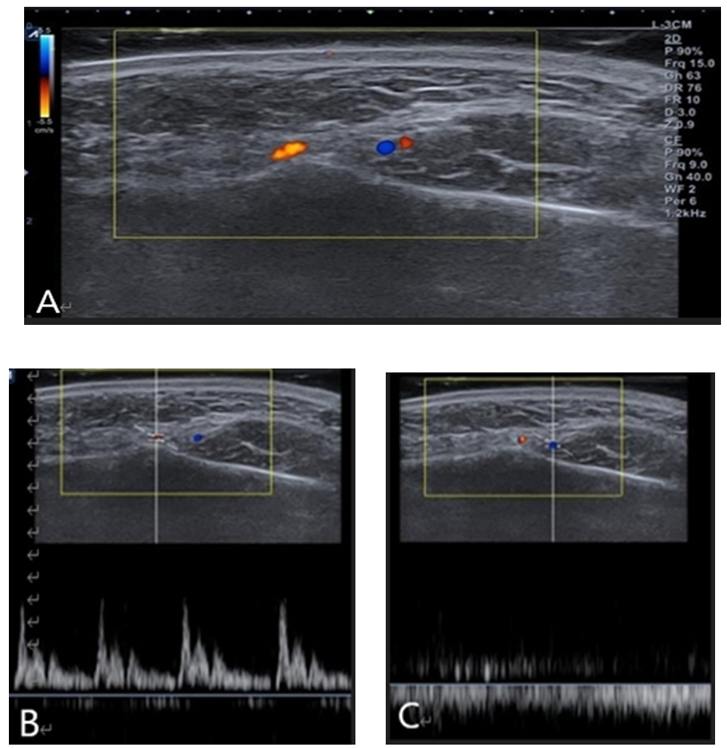

Doppler function of ultrasound devices has color doppler and power doppler pulse and is useful to observe the blood vessel condition. Doppler effect refers to a phenomenon in which the frequency of a sound wave reflected from a moving tissue is changed when a sound wave originating from a transducer returns from approaching red blood cell, the increased frequency indicates that bloodstream is coming toward the transducer, is recognized as positive, and is depicted as color red-yellow <Fig. 1>. When the reflected frequency from departing red blood cell comes in, the bloodstream is recognized as negative and is depicted as color blue <Fig. 2>.

Fig. 2. Doppler image color indication (A), and doppler power pulse image; pumping flow indicates the artery (B), and doppler power pulse image; flowing image indicates the vein (C). Yellow: artery, blue: vein